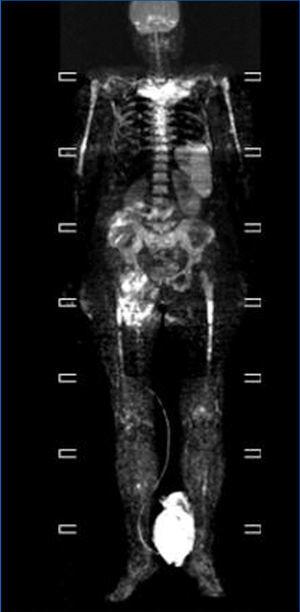

We consulted with the haematology department and performed a bone marrow biopsy that was compatible with a type MM malignant monoclonal gammopathy with intense damage and probable compacted bone marrow. The metastatic bone analysis only showed osteoporosis, and did not detect lytic lesions. The full-body MRI (Figure 2) demonstrated extensive infiltration into the marrow including in the cranium, spinal column, and diaphysis of the long bones.

In our case, this being an oligosecretory MM (with little monoclonal presence in blood and urine samples), the renal histological analysis detected the presence of cast nephropathy (myeloma kidney), which led to the diagnosis of MM. The bone marrow biopsy confirmed MM with widespread involvement. The bone analysis also did not detect images indicative of osteolysis, although the full-body MRI did find diffuse myeloma involvement (Figure 2).

Figure 2. Full-body magnetic resonance. Figure 1. Evolution of calcium, phosphorous and intact parathyroid hormone (iPTH) levels.